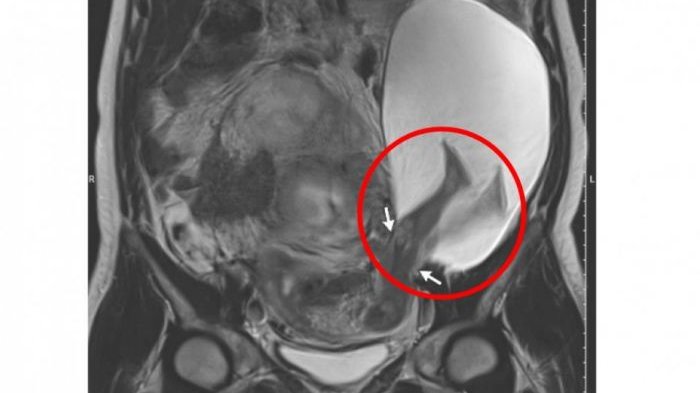

Saat di USG terlihat bahwa kaki janin sudah berada di luar rahim.

Kala itu, usia kandungan wanita yang tidak diketahui namanya ini masih berusia 22 minggu.

Namun, saat memasuki usia 30 minggu, kantung ketuban ternyata sudah membesar hingga dua kali lipat.

Parahnya, sebagian tubuh janin sudah masuk ke dalam kantung ketuban.